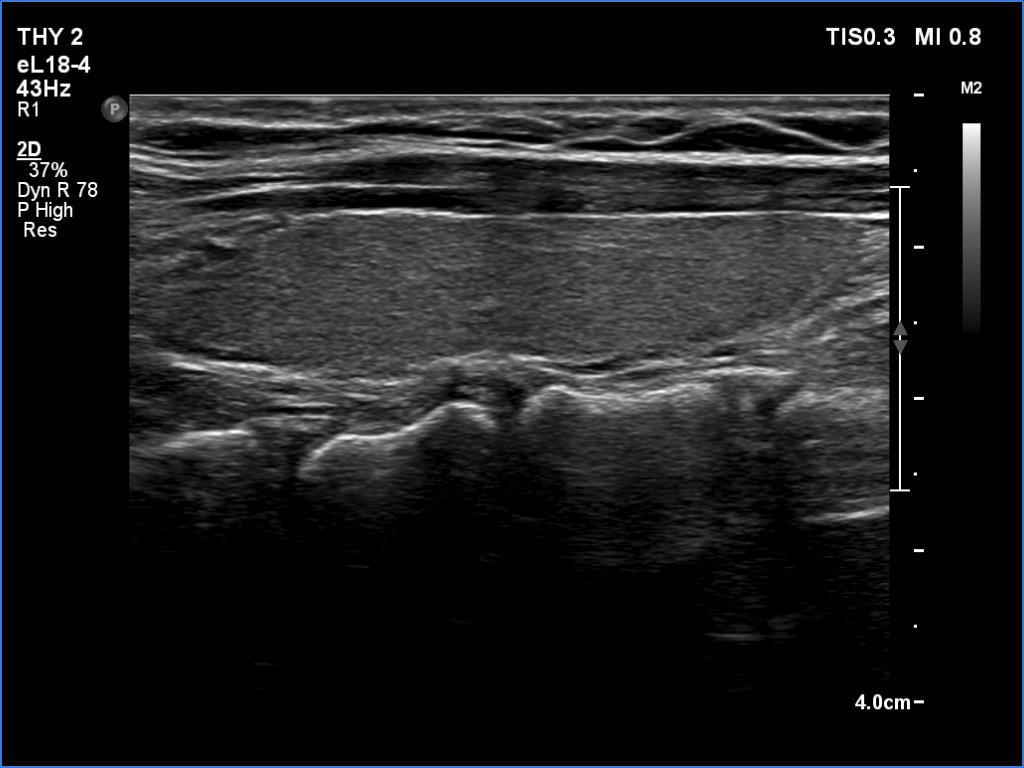

One year after surgery (second row of images):

Clinical data: The patient had no complaints.

Palpation: no abnormality.

Laboratory examination: TSH 2.05 mIU/L.

Ultrasonography. The right thyroid bed was filled with muscle fiber and connective tissue. The left lobe remained unchanged.